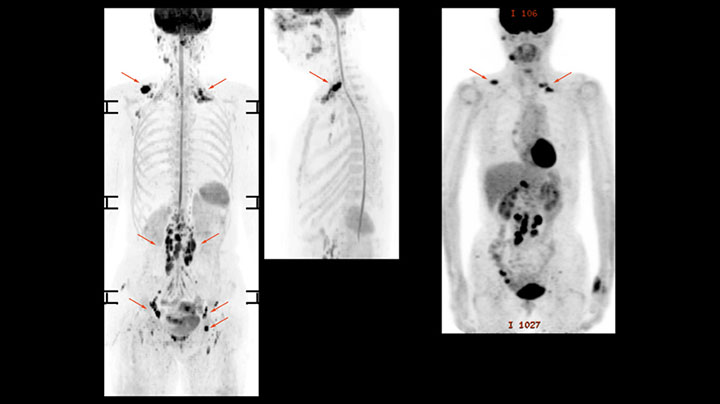

MR-Untersuchung einer 61-jährigen Patientin mit einem malignen Lymphom mit diffusionsgewichteter Ganzkörper-MRT sowie PET. Auf den gezeigten Bildern ist die Auflösung mit der diffusionsgewichteten MRT besser als mit der PET, die eine Darstellung der kleinen Beckenläsionen ermöglicht; im Halsbereich ist praktisch keine Verzerrung zu erkennen.